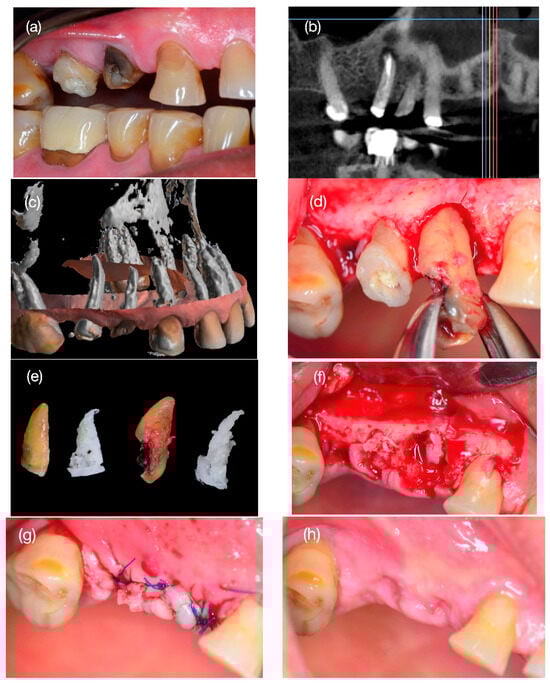

2.3. Preparation of 3D Scaffold

2.4. Step 1: Surgery Tooth Extraction and Scaffold Placement

2.5. Step 2: Bone Biopsy Surgery and Implant Installation